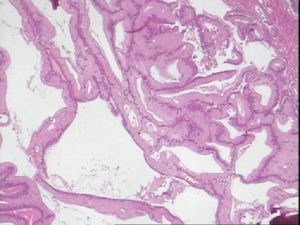

【光鏡檢查】 粘液性囊腺瘤被復高分化單層高柱狀上皮,胞漿豐富,含有粘蛋白,核位於基底。在粘液型上皮細胞間,可見杯狀細胞。約20%腫瘤含有嗜銀細胞,偶有帕內特氏細胞。若出現明顯上皮增生呈復層化(交界性腫瘤細胞不超過三層)、出芽和搭橋、核異型性及分裂相,則提示交界性腫瘤或侵蝕癌。高分化型粘液性囊腺癌被復高柱狀粘液型上皮,輕度異型,癌細胞侵入間質,腺管較規則;中度分化型,瘤細胞明顯異型,侵入間質,腺管不規則,有上皮突起結構;低分化型,癌細胞分泌粘液,呈多形性,細胞明顯異形,可見腺管樣結構。